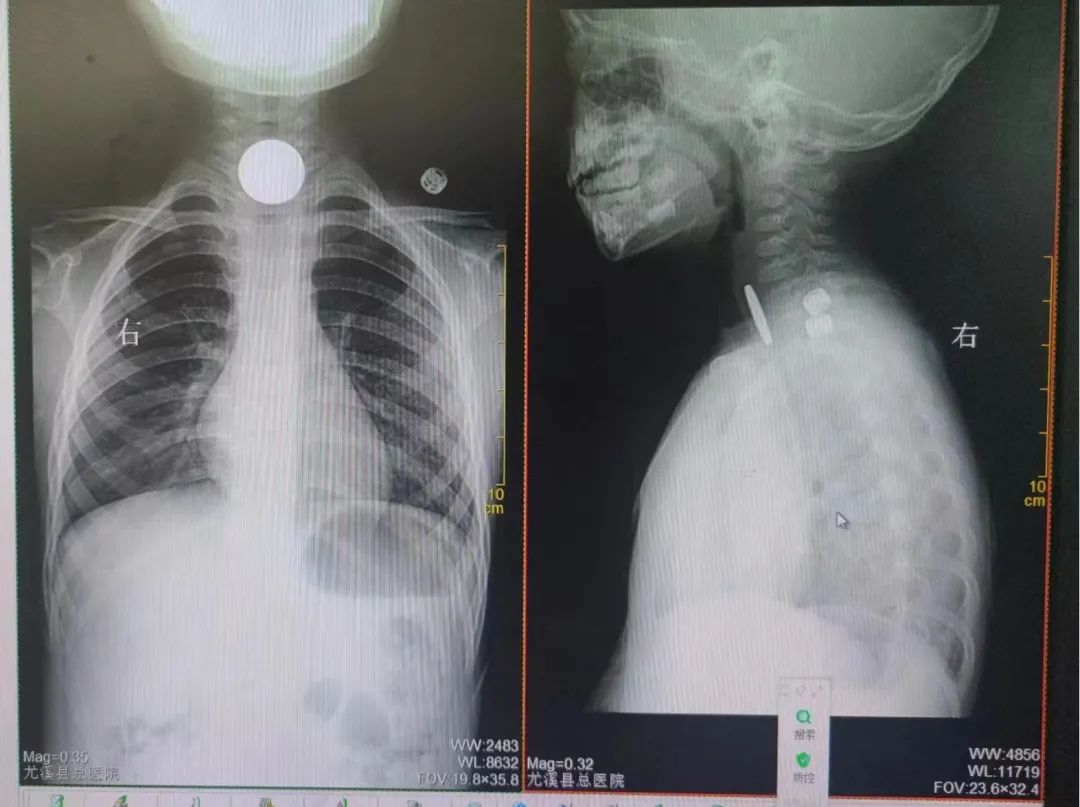

» 吞 下 一元 硬币 (99) 사진

吞 下 一元 硬币 (99) 사진

一元 硬币